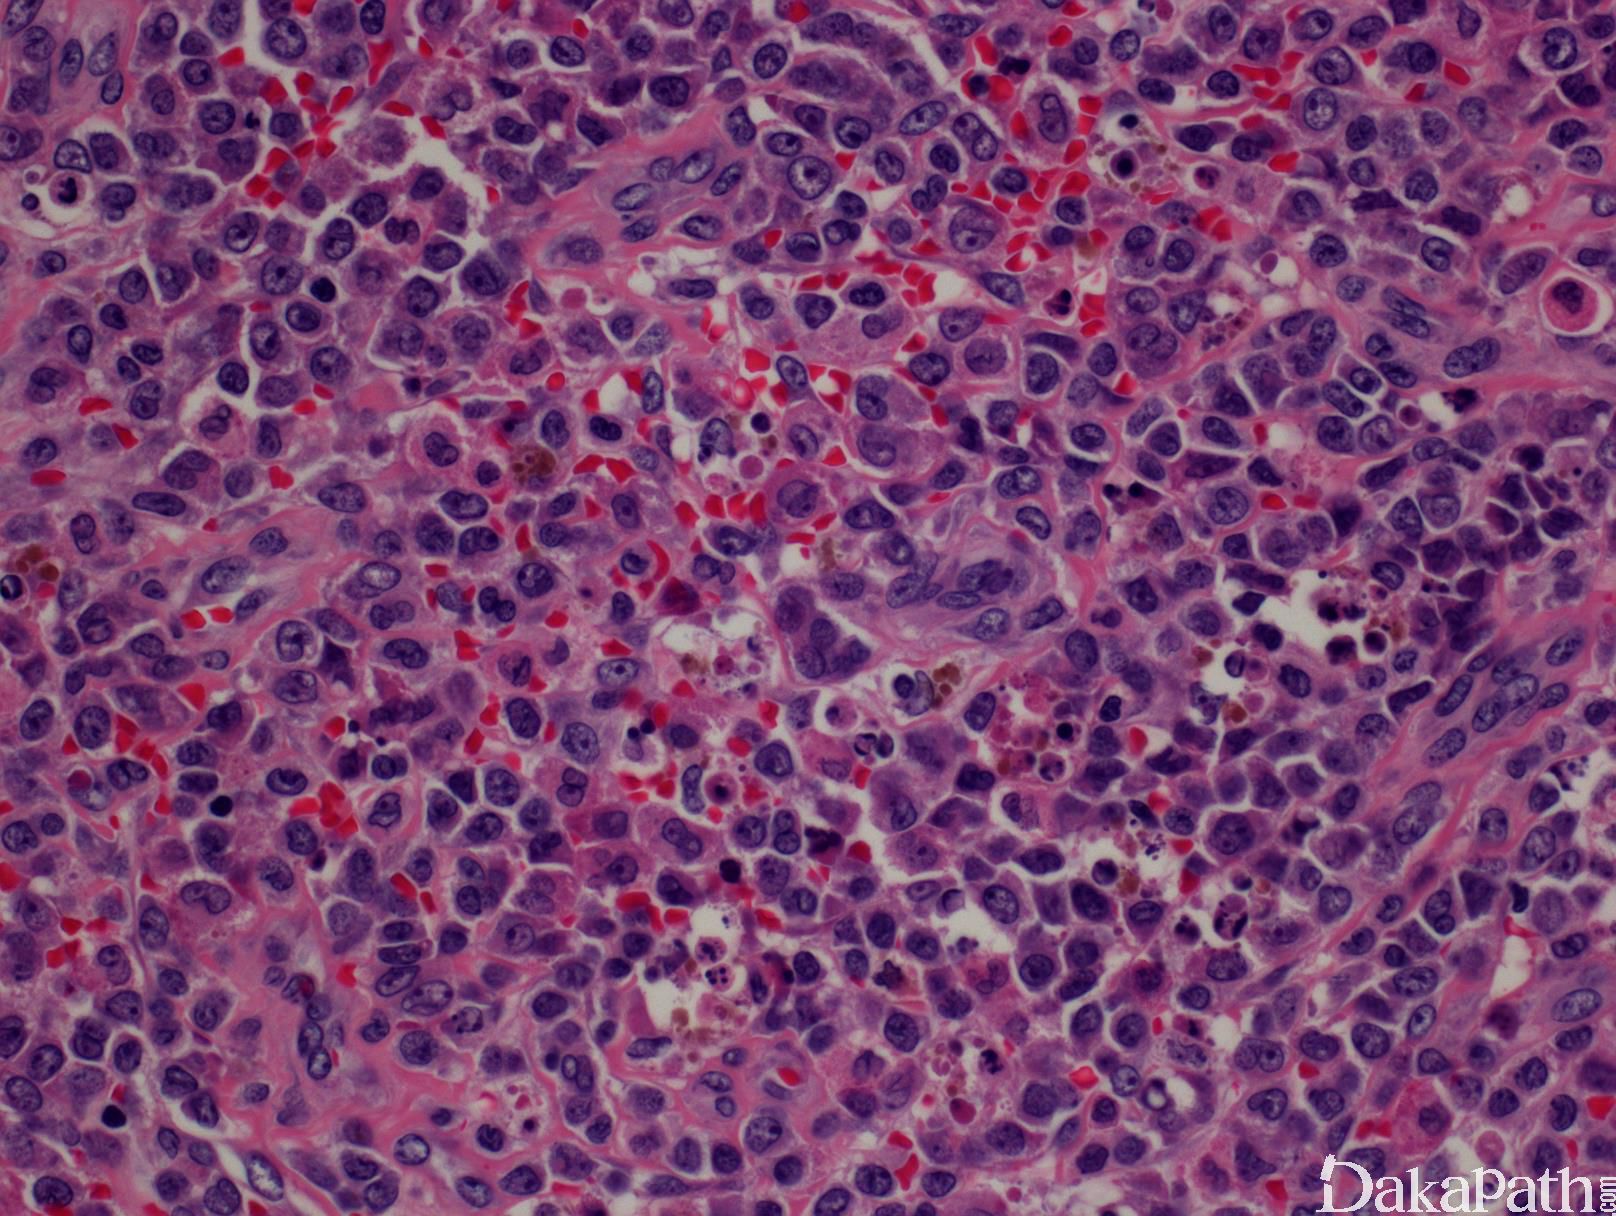

- 形态学:原始细胞弥漫增生,正常组织结构完全或部分破坏;可呈粘附性生长,类似转癌。细胞形态多为原始粒细

胞,伴或不伴幼粒或成熟粒细胞;也可以是粒-单核原始细胞或原始单核细胞。 如存在三系成分或较多红系或巨核细

胞,则要考虑髓系增生性肿瘤的急性白血病转化。